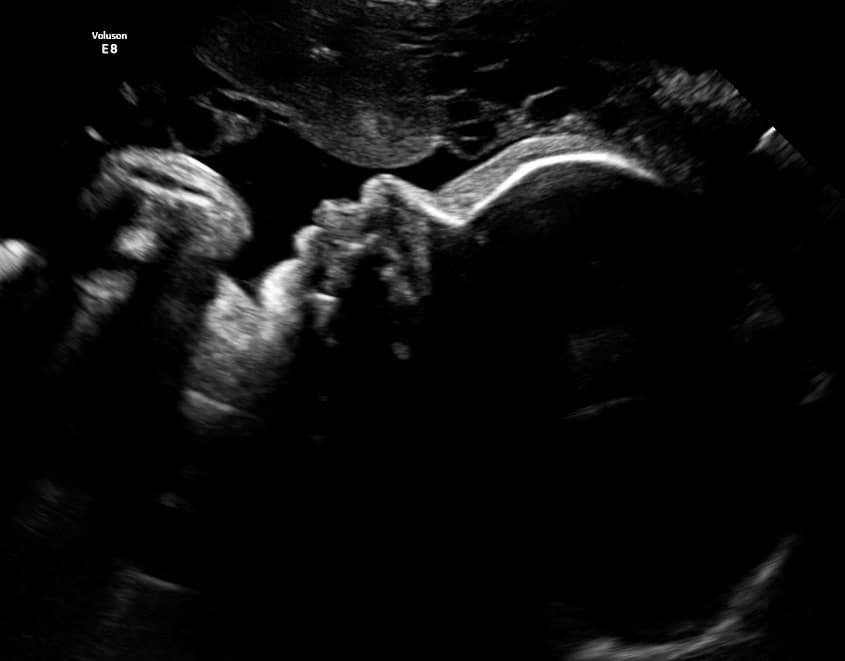

Book NowTahlequah's first 3D/4D ultrasound studio

At Magnolia Fetal Imaging, we provide a warm, relaxing environment where you can bond with your baby through advanced 3D/4D & HD ultrasound technology. Our studio focuses on capturing precious keepsake moments for families — gender reveals, early looks, and high‑definition images you will cherish for a lifetime.

All sessions are non‑diagnostic and designed purely for bonding and keepsake entertainment.